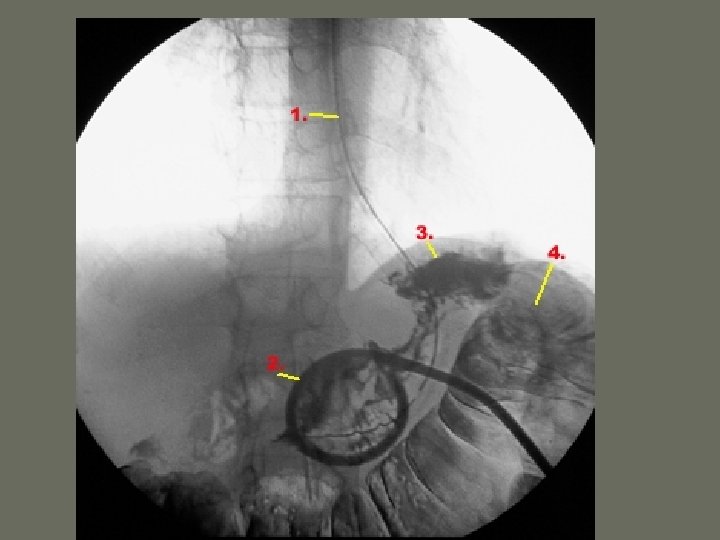

Interventional Procedures • Non-vascular procedures include: 1. Percutaneous Nephrostomy Tube – catheter is introduced through the _____, into the kidney and into the renal pelvis – may be used to remove _____, drain fluid or other interventions

Interventional Procedures 6. Ureteric Stent Placement • Inserted in ureter • performed after a percutaneous nephrostomy • used on patients with ________ of the renal system

Interventional Procedures 7. Percutaneous Lithotripsy • extracorporeal shock wave lithotripsy (ESWL) • renal stone is obliterated until they are ______ enough to pass through the urinary system